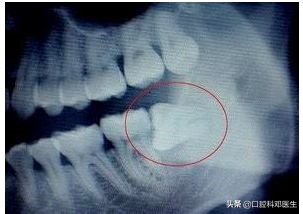

在远古时代,由于贫穷,伙食差,人类都不给他作案的机会,有足够的位置让他长出来,到了现代,随着伙食的精细,智齿常常发育不良,不是东倒就是西歪,为了报复主人,时不时发炎疼痛,让主人记住我,或者挖洞,把兄弟给祸害!

智齿行凶过程图